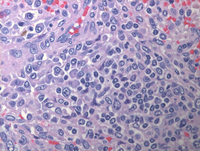

HE images of splenectomy

At low power, multiple discrete white pulp nodules are noted. On higher power these nodules are monotonous with replacement of the white pulp by small to medium sized lymphoid cells with occasional plasmacytoid cells.